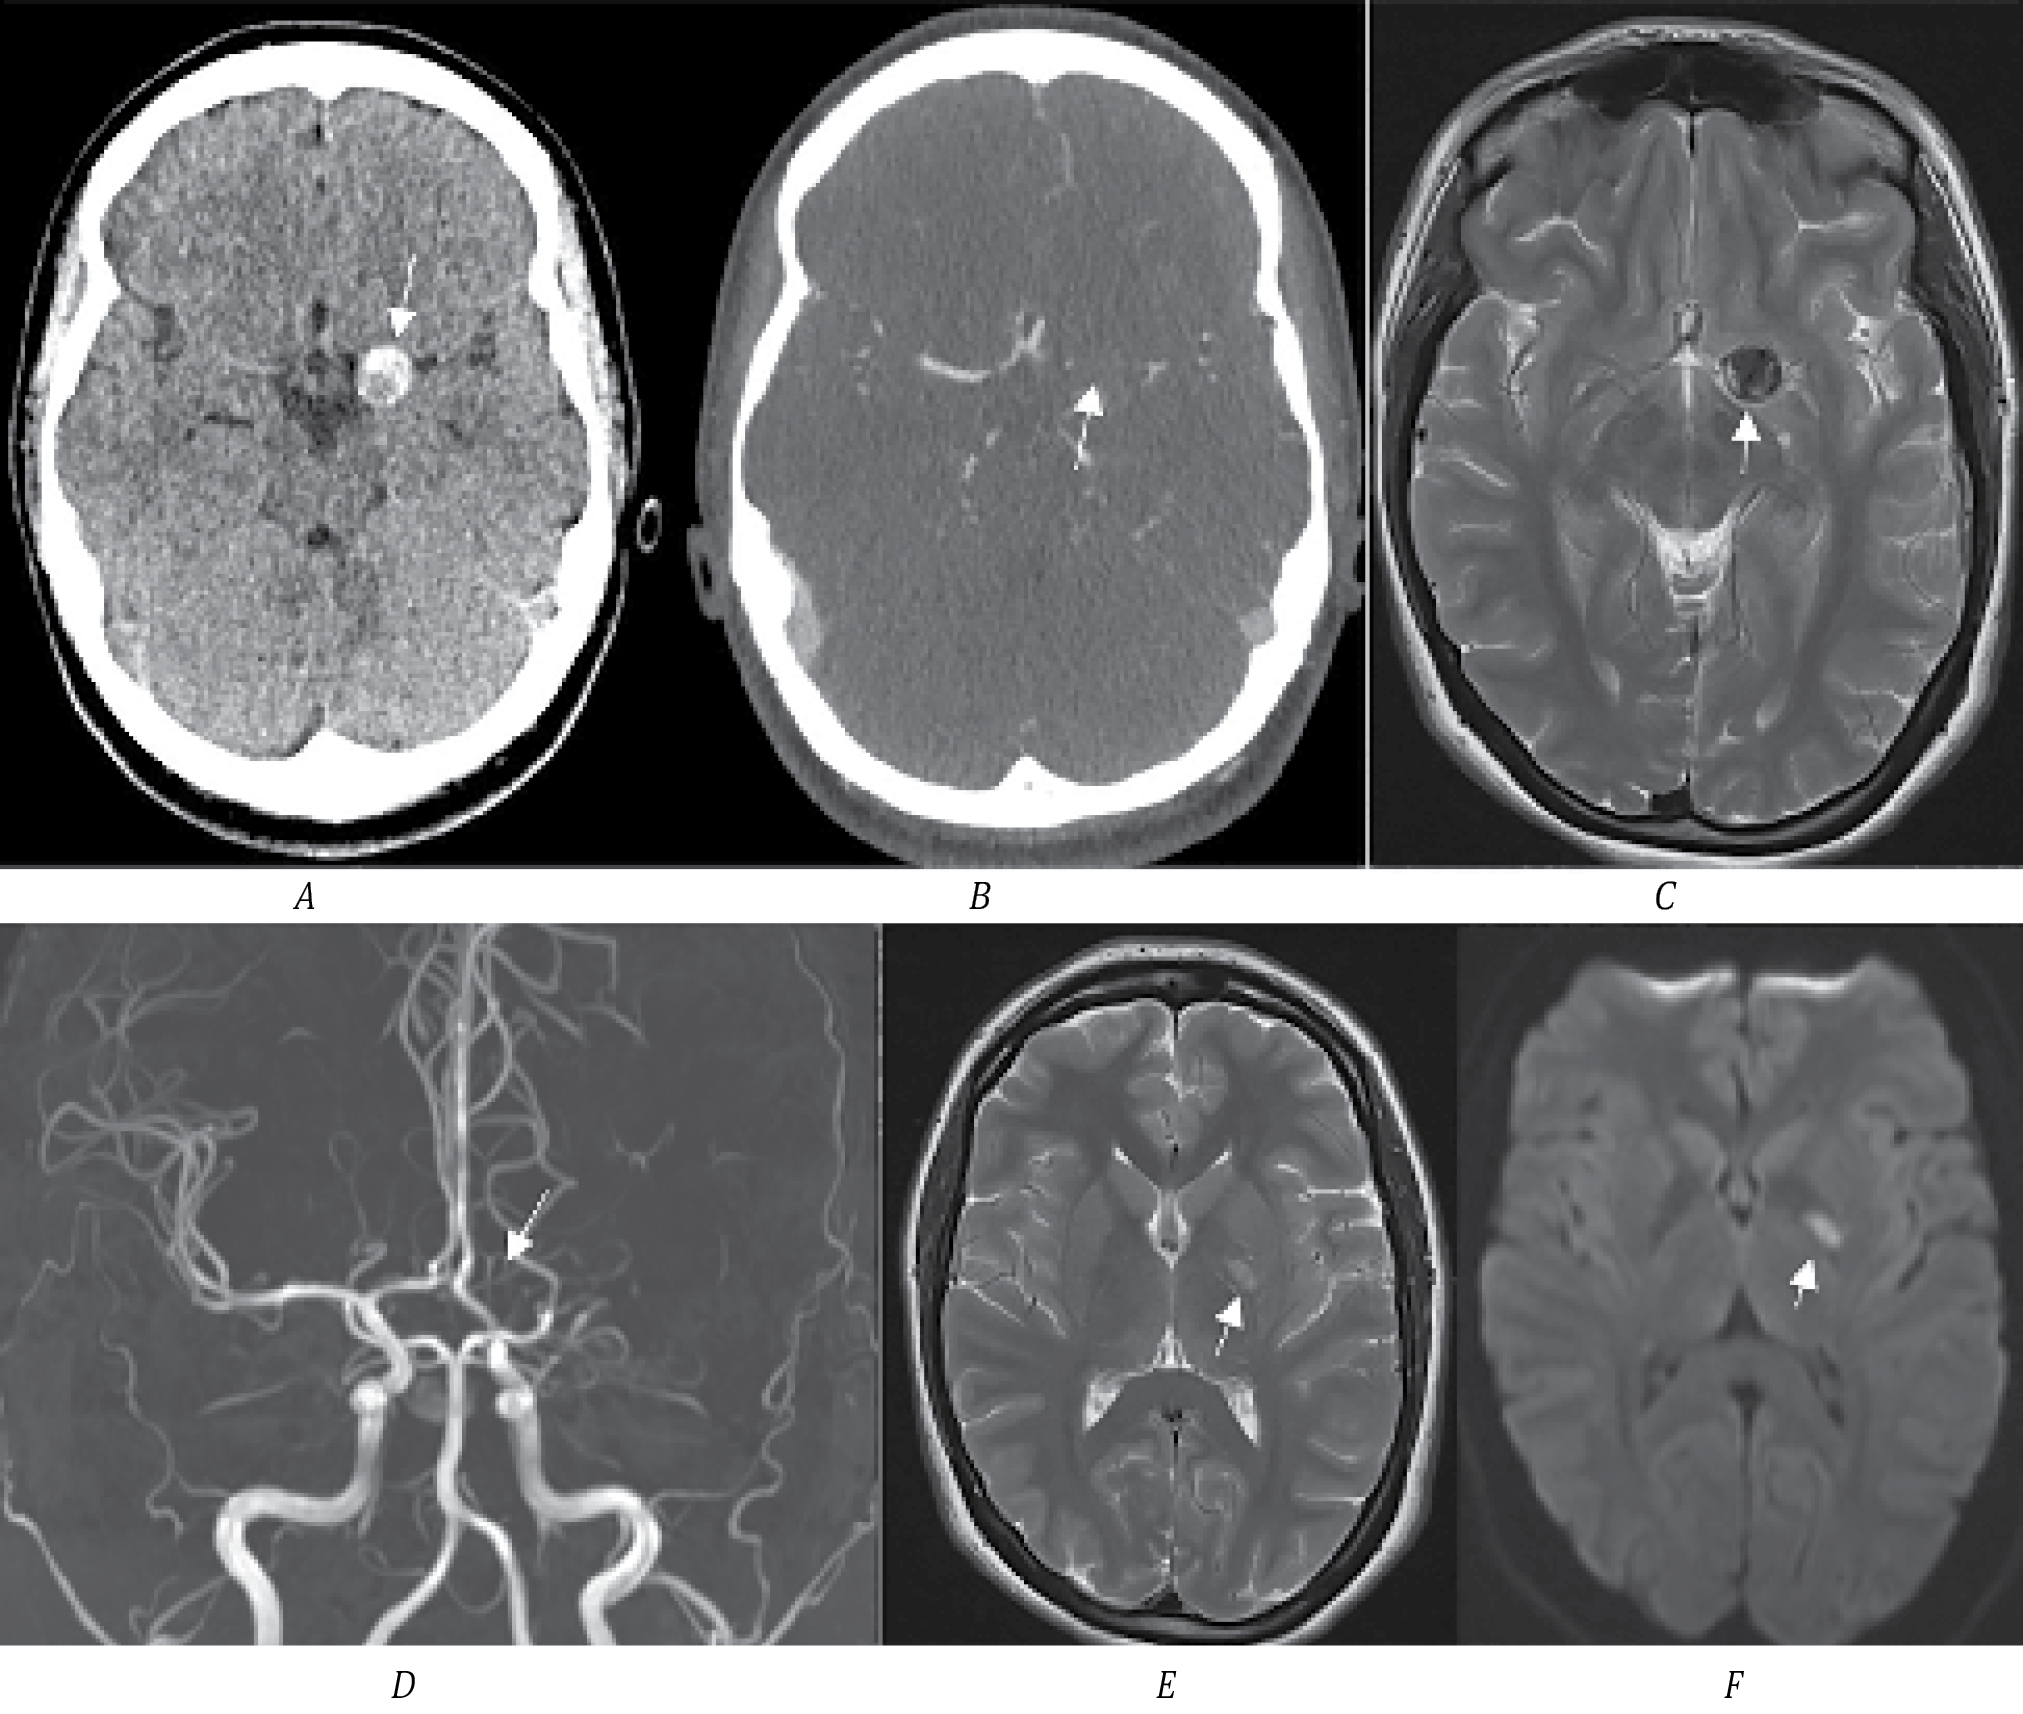

Пациент К., 62 года, поступил в первичное сосудистое отделение с клиникой правостороннего гемипареза (2 балла в руке, 3 — в ноге), моторной афазией, 16 баллов по NIHSS. По МСКТ определяется зона ишемии в левой лобной доле с распространением на подкорковые структуры. По нативному исследованию заподозрена ТА СМА размером до 2 см (рис. 2, А, B). По неясным причинам в первичном сосудистом отделении МСКТ-ангиография не выполнялась. Через 3 мес направлен в региональный сосудистый центр. По МСКТ определяется зона кистозно-атрофических изменений в области перенесённого ИИ в левой лобной доле. По МСКТ-ангиографии определяется небольшая функционирующая часть аневризмы М1-сегмента, дистальные ветви СМА проходимы (рис. 2, C, D).

Рис. 2. МСКТ головного мозга пациента К.

А — МСКТ-натив, определяется зона ишемии в левой лобной доле; B — стрелкой указана ТА СМА с кальцификацией размером до 2 см; C — МСКТ через 3 мес после перенесённого ИИ, определяется зона кистозно-атрофических изменений в левой лобной доле; D — МСКТ-ангиография, белой стрелкой обозначена функционирующая часть аневризмы, чёрной — контур тромбированной части; E — 3D-реконструкция МСКТ-ангиографии, стрелкой указана функционирующая часть аневризмы.

С учётом наличия большого тромбированного мешка аневризмы в области М1-сегмента СМА и развития ишемии в области кровоснабжения лобной М2-ветви СМА вероятна эмболия тромбов из мешка аневризмы. В динамике через 3 мес по ангиографии определяется проходимость всех ветвей СМА, что могло быть связано с наступившей реканализацией тромбированной ветви. При дообследовании других факторов риска ИИ, кроме гипертонической болезни, у пациента не обнаружено. Учитывая высокий риск повторных тромбоэмболических осложнений, выполнили микрохирургическое клипирование аневризмы. После операции состояние пациента декомпенсировалось в связи с развитием энцефалопатии; выписан из стационара с оценкой по модифицированной шкале Рэнкина 4.

Клинический случай 3

Пациентка И., 22 года, доставлена скорой помощью с жалобами на слабость и неловкость в правых конечностях. На момент осмотра — в ясном сознании, правосторонний гемипарез до 3,5 балла в руке, 4 баллов в ноге. По МСКТ определяется округлое образование гиперденсной плотности в проекции сильвиевой щели, подозрение на ТА. Обращает на себя внимание, что образование имеет разную плотность, в том числе участок высокой плотности, как возможный признак острого тромбоза (рис. 3, А). По МСКТ-ангиографии отсутствует кровоток в СМА слева, функционирующей части аневризмы не определяется. Учитывая лёгкий неврологический дефицит (5 баллов по NIHSS), острый тромбоз аневризмы СМА вместе с несущей артерией маловероятен. Пациентке выполнено МРТ головного мозга. Определяется большая ТА СМА, тромбоз СМА на всём протяжении. В области внутренней капсулы определяется участок ишемии, который соответствует развившемуся неврологическому дефициту у пациентки. На основании этого вероятно, что тромбоз аневризмы СМА вместе с артерией является хроническим, а в настоящее время клиническая картина вызвана развитием ишемии в подкорковых структурах, кровоснабжаемых лентикулостриарными артериями. Механизм развития ишемии в данном случае может быть связан как с эмболией тромбами, так и с увеличением размера аневризмы (наличие свежего тромба) и механическим перекрытием артерий.

Рис. 3. МСКТ головного мозга пациентки И.

А — стрелкой обозначена ТА; B — МСКТ-ангиография, белой стрелкой обозначено отсутствие кровотока в левой СМА; C — МРТ Т2-ВИ, стрелкой обозначена ТА СМА; D — МР-ангиография, отсутствие кровотока в СМА слева (указано стрелкой); E, F — МРТ Т2-ВИ и DWI, стрелкой обозначен очаг ишемии в области внутренней капсулы.

Других факторов риска инсульта у молодой пациентки не выявлено. Для определения тактики ведения выполнена церебральная ангиография и МСКТ-перфузия. По данным ангиографии у пациентки хорошо развит коллатеральный кровоток. По данным МСКТ-перфузии значимой разницы капиллярного кровотока в обоих полушариях нет. Принято решение о консервативном ведении пациентки с динамическим ангиографическим контролем. Осмотрена в динамике через 6 мес, повторных эпизодов ишемии у пациентки не было, функциональный статус оценён как 0 баллов по модифицированной шкале Рэнкина. На фоне приёма антиагрегантной терапии по МСКТ-ангиографии признаков реканализации аневризмы и средней мозговой артерии нет.